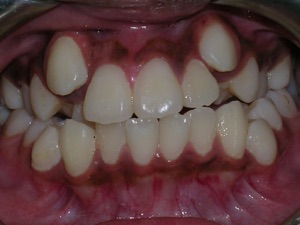

Here’s a young lady who presented with severe crowding. Often we think of crooked teeth as being limited to front teeth. Here one can see that back teeth can also get crowded. Braces were placed and select teeth were removed. Watch.